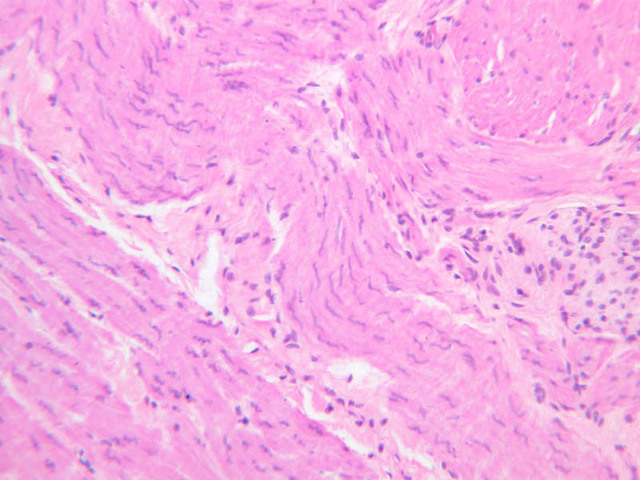

Sections of esophagus appear on slides B-2 (H&E [2.5x-labeled, 10x-labeled, 20x-labeled, 40x] [20x, 20x. 20x]) and B-3 (H&E [2.5x-labeled, 20x, 20x, 10x]). By studying these sections, you will be able to familiarize yourself with the basic structural plan of the entire digestive tube. Find the esophageal lumen and identify the three components of the mucosa (mucous membrane): a stratified squamous (nonkeratinized) epithelium, a layer of loose connective tissue (lamina propria) and a thin double layer (inner circular/outer longitudinal) of smooth muscle, known as the muscularis mucosae. The submucosa, which consists largely of dense irregular connective tissue, lies beneath the mucosa. Carefully scan the submucosa to find ganglion cells and bundles of nerve fibers that comprise Meissner's plexus (submucosal plexus). You may also find mucous glands (esophageal glands proper) in the submucosa. The muscularis externa lies beneath the submucosa. In the esophagus, the muscularis externa consists of an inner circular and an outer longitudinal layer of muscle. Note that at the mid-esophageal levels represented by these slides, the muscularis externa consists of a mixture of smooth and skeletal muscle. What kind of muscle would you expect to find in the upper esophagus? In the lower esophagus? Between the two layers of the muscularis externa you should be able to find ganglion cells and nerve fibers of Auerbach's plexus (myenteric plexus). External to the muscularis externa is a layer of connective tissue, the tunica adventitia, which binds the esophagus to surrounding structures.